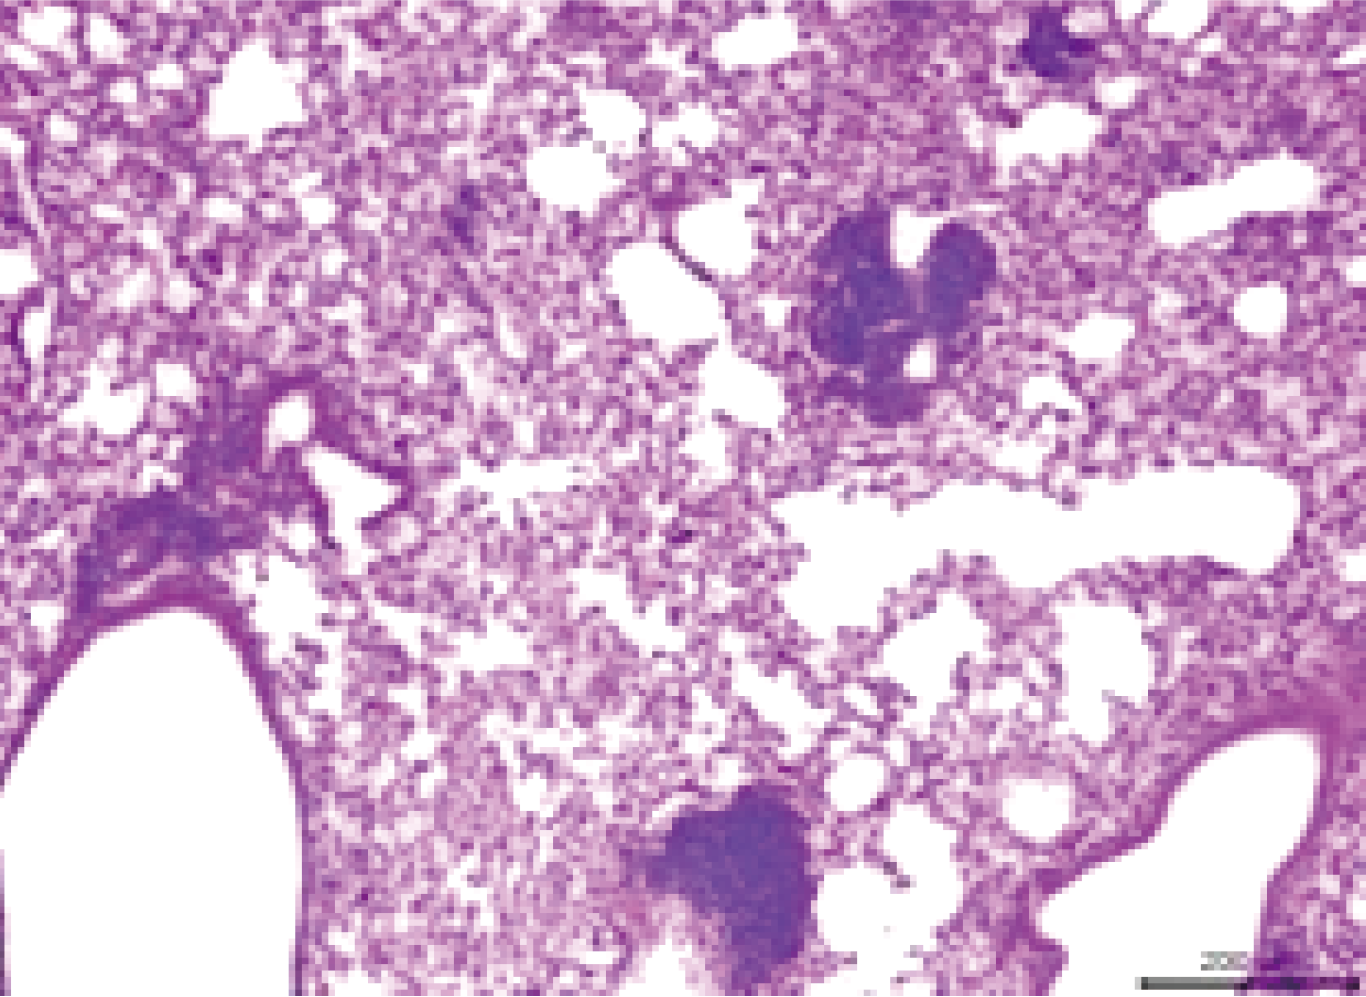

Pathological Criteria:

Model animal muscle tissue shows diffuse inflammation, characterized by necrosis and fragmentation of muscle fibers, inflammatory cell infiltration, possibly accompanied by interstitial edema.